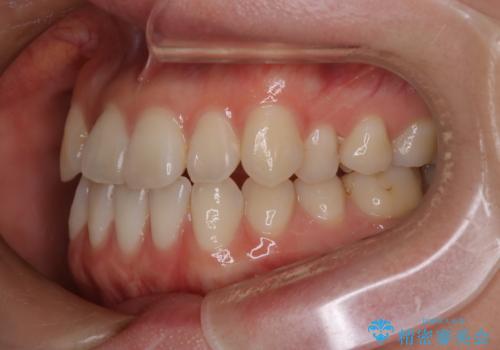

- 八重歯と、右上前歯(2番)が下の歯より内側に入っている反対咬合を気にされてご来院されました。精密な検査の結果、八重歯と反対咬合を同時に改善するためには、歯列全体にスペースを確保する必要があると判明。患者様のご希望から、透明で目立たないインビザライン(マウスピース矯正)による治療計画を立案しました。奥歯全体を奥へ動かす遠心移動でスペースを作り、これらの複雑な問題を一括で解消することを目指します。

今回の矯正治療では、透明なマウスピース型の装置インビザラインを使用しました。治療は、緻密なデジタル計画に基づき、奥歯から順に歯列全体を後方へ移動させる遠心移動を実施。これにより、八重歯を正しい位置に並べるためのスペースを確保しました。同時に、右上の2番を前方に誘導することで反対咬合を解消。結果として、抜歯することなく八重歯と反対咬合という複数の問題が改善され、機能的で美しい歯並びを獲得していただけました。